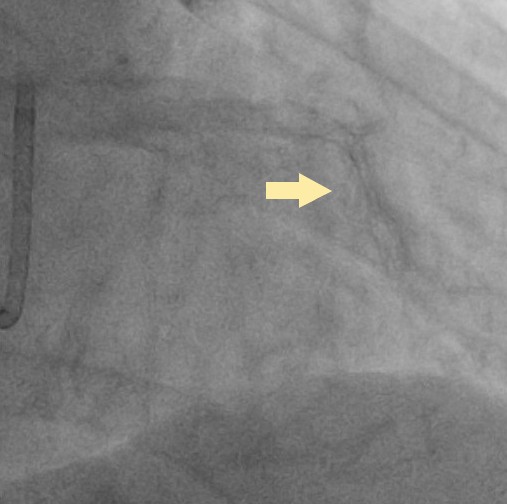

Initially, we tried to insert IVUS catheter but unable to cross the lesion. We tried a NC balloon but unable to cross it also.Hence, we used rotational atherectomy with 1.5mm burr. However, the burr was unable to cross lesion even in high speed and entrapped in the stent.We removed the burr in guide extension catheter then the NC balloon could cross the lesion. The IVUS cather could also cross it with guide extension catheter support. The stent was almost not expanded. We tried NC balloon high pressure dilation but balloon slippage and burst. The lesion was still un-dilatable. We insert cutting balloon which avoided slippage but remained burst. We escalated the burr size to 1.75mm. The larger burr was not stucked but still unable to cross lesion. Besides, the larger burr causing slow blood flow. After adenosine injection, the patient's blood flow recovered. We reduced the burred size to 1.25mm which cross the lesion once but entrapped while doing polishment. After burr retrieval, we used NC balloon high pressure dilation. The balloon bursted but the lesion remained un-dilatable.Finally, the lithotrypsy balloon could cross the lesion and eliminate 80 pulses. The lesion was expanded much well. The IVUS showed the old stent was expanded and calcium was cracked. We deployed a new stent for old one destruction and proximal dissection. The final IVUS image showed epansion and apposition were accpetable.